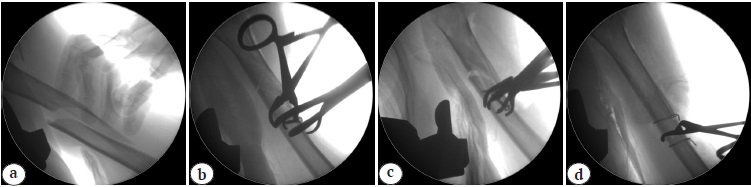

The first step was passing the lag screws through the diaphyseal part of the fracture; however, satisfactory repositioning was not achieved. The lag screws were removed and two cerclage sutures were applied (Fig. 2). Then osteosynthesis was performed with a long PHILOS plate (Synthes) (Fig. 3).

Fig. 3. Postoperative X-ray’s after osteosynthesis of the humerus with a PHILOS Long plate and cerclages: a — frontal view; b — lateral view; c — oblique view